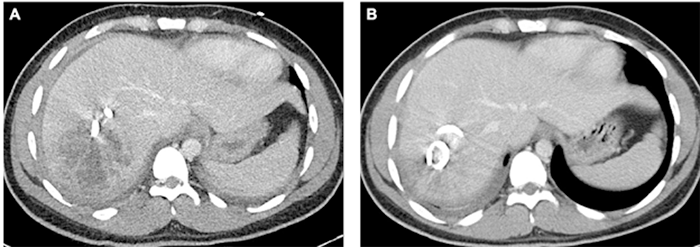

Magnetic resonance imaging (MRI) demonstrated an 8 × 8 × 7 cm irregular, heterogenous lesion in the right lobe of the liver suggestive of an intrahepatic abscess. A hypermucoviscous strain of Klebsiella pneumoniae was isolated from the blood. Despite antibiotic administration with ceftriaxone and metronidazole, the patient remained septic. A 14 French percutaneous drain was placed by radiologic guidance into a 7.6 cm gas-containing complex collection in the right hepatic lobe; however, the drain had minimal output. Repeat CT two days post-procedure confirmed appropriate drain placement but no decrease in the size of the intrahepatic abscess (Figure 3A). Klebsiella pneumoniae was isolated from cultures obtained from the hepatic abscess and was found to have a positive string test. The CT also revealed a perihepatic extension of the abscess, a pelvic fluid collection, and a dilated appendix associated with fat stranding, consistent with acute appendicitis, which was a possible source of the patient's liver abscess. On hospital day 12, the surgical team elected to manage the acute appendicitis nonoperatively and the abscess collections by the radiologic-guided placement of two additional 12 French percutaneous drains. The patient improved gradually over the next four days with resolution of fever and leukocytosis on hospital day 16. On hospital day 19, repeat CT demonstrated near-complete resolution of the intrahepatic abscess (Figure 3B). The right hepatic and pelvic drains were removed at discharge, and the perihepatic drain was and removed three weeks after discharge. The patient fully recovered after a four-week course of outpatient IV ceftriaxone.

Figure 3. Radiographic Images From Case 2. Published with Permission

A) Transverse section of CT chest/abdomen/pelvis obtained two days after radiologic-guided drain placement demonstrating 7.6 cm × 6.5 cm complex collection in right hepatic lobe with pigtail percutaneous drain along medial aspect of collection; B) transverse section of CT chest/abdomen/pelvis from obtained 26 days after initial drain placement, demonstrating near resolution of intrahepatic fluid collection